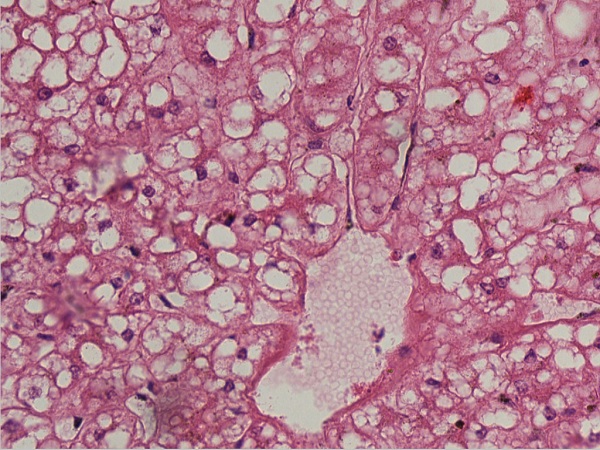

肝脂变1